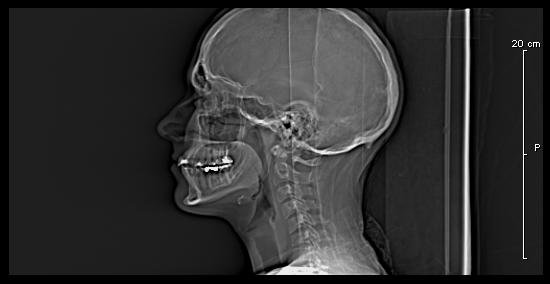

Кости черепной коробки выполняют важнейшую функцию — защищают от внешнего воздействия головной мозг. Рентген черепа может быть назначен врачами разных специализаций (неврологом, онкологом, отоларингологом, терапевтом и др.) в рамках комплексной диагностики заболевания или с целью контроля эффективности проводимых лечебных мероприятий (в том числе и после оперативного вмешательства).

Обследование костей черепа может быть назначено в качестве способа диагностики таких патологий как черепно-мозговые травмы (в том числе и родовые) и их последствия — гематомы, опухоли, кисты, измененные показатели внутричерепного давления. Рентгенографию применяют для выявления доброкачественных опухолей головного мозга (менингиомы), костей черепа (остеомы) и злокачественных образований и их метастаз. Другими показанием к обследованию является воспаление оболочки головного мозга, разнообразные патологии лор-органов (например, гайморит в тяжелой форме), врожденные и приобретенные аномалии развития.

На рентгенограмме хороши видны признаки сотрясения головного мозга и последствия хронической внутричерепной гипертензии (повышенного давления), например увеличение турецкого седла. Подробное исследование данной области используется в рамках диагностики патологий гипофиза.

Показаниями к назначению рентгена являются регулярные головные боли невыявленной этиологии, головокружения и потери сознания, тремор рук, регулярные носовые кровотечения, изменение функций слуха, зрения, обоняния, болевые ощущения во время пережевывания пищи. Непрямыми показаниями являются признаки изменений гормонального фона (при подозрениях на опухоль гипофиза или головного мозга), различные нарушение моторных или когнитивных функций, неврологическая симптоматика (нарушения сна, перепады настроения или изменения эмоционального фона и др.).